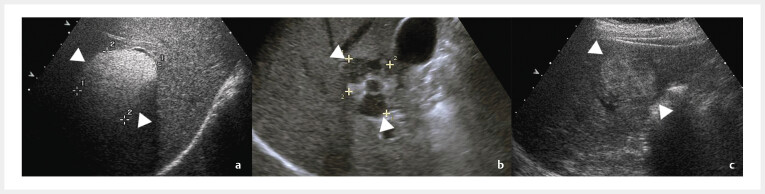

Purpose  This study aimed to compare contrast-enhanced ultrasound (CEUS) features of hepatic angiomyolipoma (HAML) and challenging cases of HCC, mainly those with no hepatitis infection but also with a low level of AFP (non-viral AFP- HCC). Materials and Methods  The study included pathologically confirmed HAMLs and non-viral AFP- HCCs undergoing CEUS from 2012 to 2023. Sonovue (SV) CEUS and Sonazoid (SZ) CEUS characteristics of the two groups were compared. Results  The study included 50 HAMLs (24% on SZ-CEUS) and 88 non-viral AFP- HCCs (21.6% on SZ-CEUS). The CEUS characteristics on SZ-CEUS were similar to those on SV-CEUS to a certain extent. HAMLs more frequently displayed no washout and partial washout with partial no washout, so-called PWNW, in the late phase and post-vascular phase, whereas HCCs more commonly exhibited mild washout. In the post-vascular phase, all non-viral AFP- HCCs exhibited washout, thereby facilitating differentiation from no-washoutHAMLs, superior to SV-CEUS, where some non-viral AFP- HCCs still exhibited no washout in late phase that could not be distinguished from HAMLs. It is noteworthy that PWNW was exclusively found in nodules exhibiting hyper- and hypoechoic separation of the nodules, and hyper- and hypoechoic separation of HAMLs in the post-vascular phase on SZ-CEUS demonstrated PWNW more frequently compared to the late phase, which can potentially help distinguish nodules with hyper- and hypoechoic separation as either HAML or non-viral AFP- HCC. Conclusion: This study highlighted the usefulness of SV- and SZ-CEUS for distinguishing HAML and non-viral AFP- HCC and filled in existing gaps regarding the SZ-CEUS features of HAML.

Abstract Image